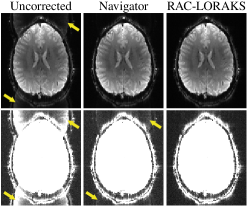

Supporting Information Figure S1: Illustration of EPI ghost correction. The top row of this figure shows EPI images obtained from different methods, while the bottom row shows the same images with 10 intensity amplification to highlight the ghost characteristics. If EPI data is naively reconstructed without accounting for the systematic differences between data acquired with positive and negative readout gradient polarities (“Uncorrected”), then strong Nyquist ghosts appear in the image as indicated with arrows. Modern EPI techniques frequently try to eliminate these artifacts using navigator information to estimate the systematic differences between the data collected with different readout polarities. In the navigator-based example we show (“Navigator”), the navigator information was collected using a 3-line EPI acquisition with the phase encoding gradients turned off, and the difference between positive and negative gradient polarities was modeled using constant and 1D linear phase terms. Although this approach substantially reduces Nyquist ghosts, it is common for some amount of residual ghosting to still be present in the images, particularly in cases where simple 1D phase modeling is inadequate to capture the differences between the two gradient polarities. We also show an example of our proposed approach (“RAC-LORAKS”), which can account for more complicated variations between the different gradient polarities, and which is substantially more successful at suppressing Nyquist ghosts in this example.